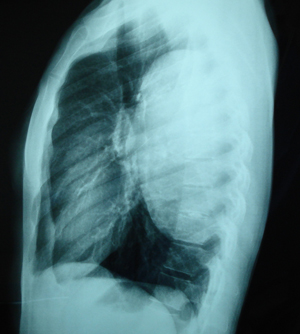

Εικόνα 2

Πλάγια ακτινογραφία θώρακος, στην οποία διακρίνεται μάζα στον οπισθοστερνικό χώρο στο ανώτερο πρόσθιο μεσοθωράκιο.